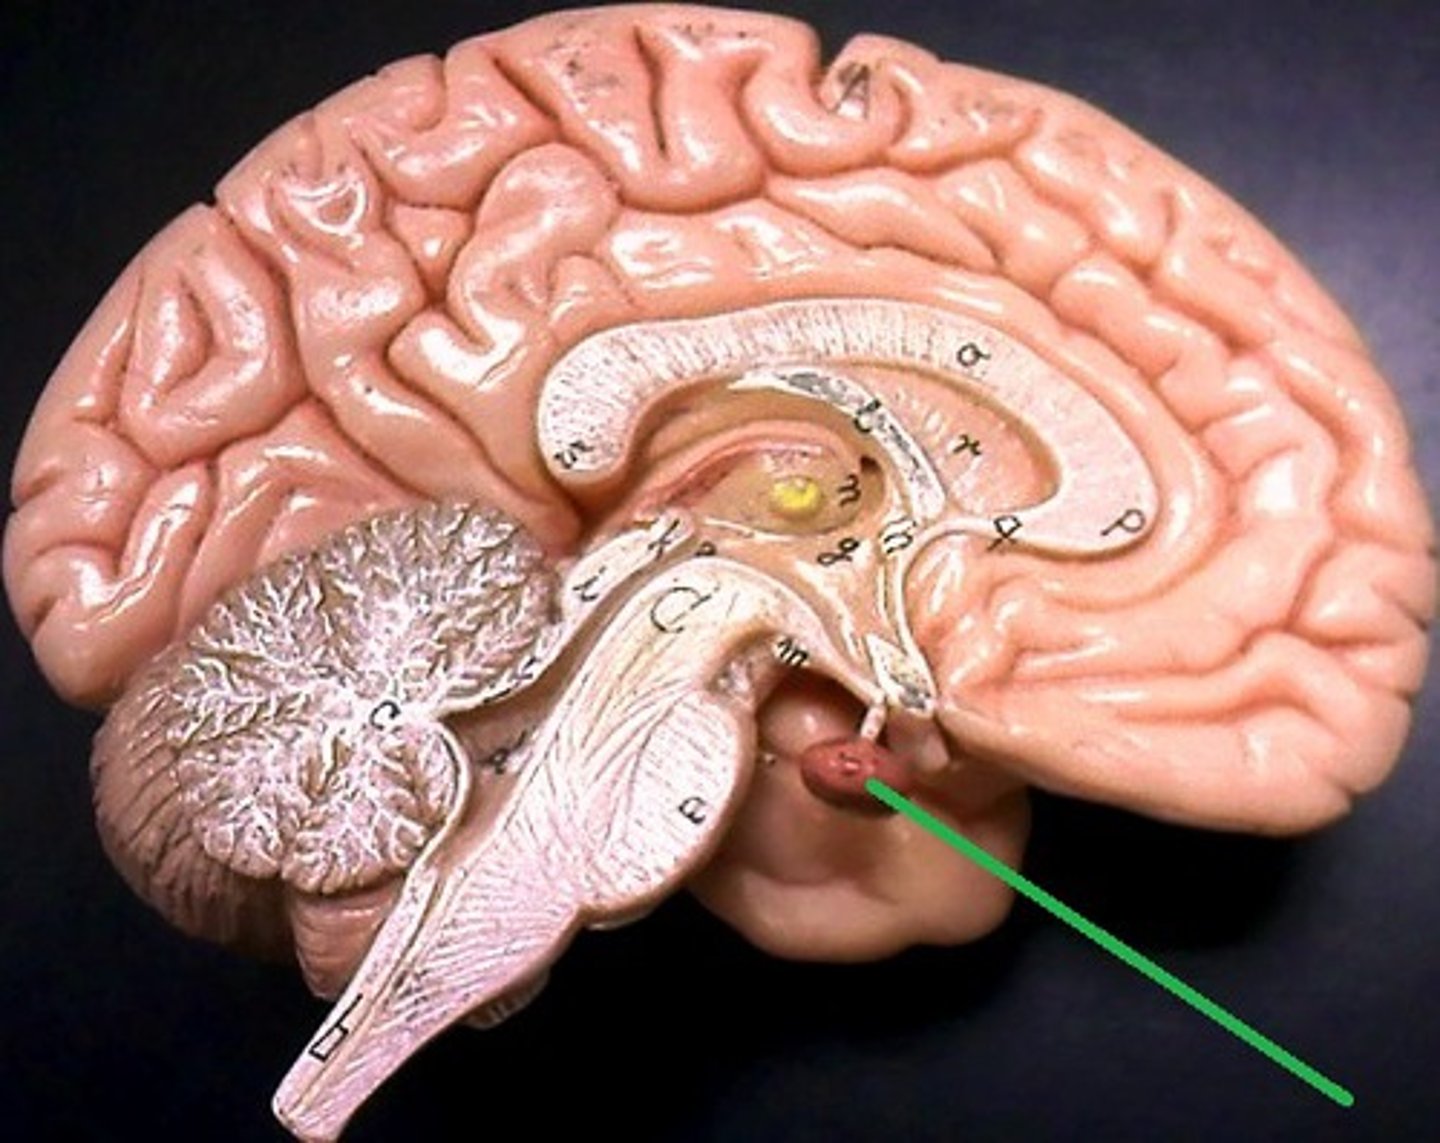

pituitary gland

mammillary bodies

infundibulum